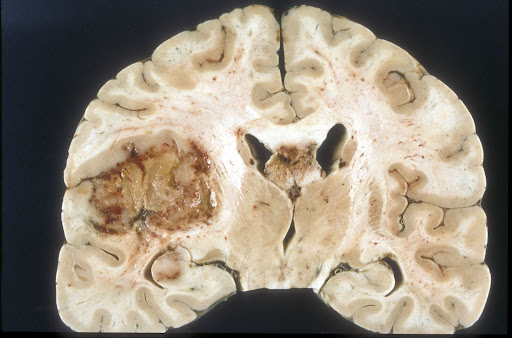

The researchers first sampled over 600,000 adult patients logged in the national Surveillance, Epidemiology, and End Results (SEER) database and National Cancer Database (NCDB) over a roughly 40 year span. The total sample included over 400,000 patients with benign brain tumors (meningiomas, pituitary adenomas, and vestibular schwannomas) and nearly 200,000 with malignant brain tumors (glioblastomas, astrocytomas, and oligodendrogliomas). This patient pool was then categorized by race, insurance status, and a residence-based rural-urban continuum code. Finally, regression and multivariable analyses were applied to identify demographic characteristics associated with recommendations that did not include or were against clinically indicated surgery.

The researchers found that Black patients, in particular, were less likely to be recommended to pursue surgery for four types of brain tumors: all three benign tumors and glioblastoma, a cancerous and typically life-threatening tumor. Specifically, Black patients were found to collectively be 14% to 19% less likely to receive the indicated resection procedure for malignant tumors and up to 48% less likely to receive it for benign tumor conditions, even after other clinical factors (including determination of the localization, size, and stage of the tumors examined) were statistically accounted for. However, while largely unexplained by other demographic factors, this evident racial divide in recommendations improved over the 40 years examined and effectively closed in the most recent decade included (2010-2017). While this offers hope that the influence of potential implicit racial biases over clinical decision-making is diminishing, work to eliminate them remains unfinished.

[2] Image retrieved from: https://commons.wikimedia.org/wiki/File:Glioblastoma_macro.jpg